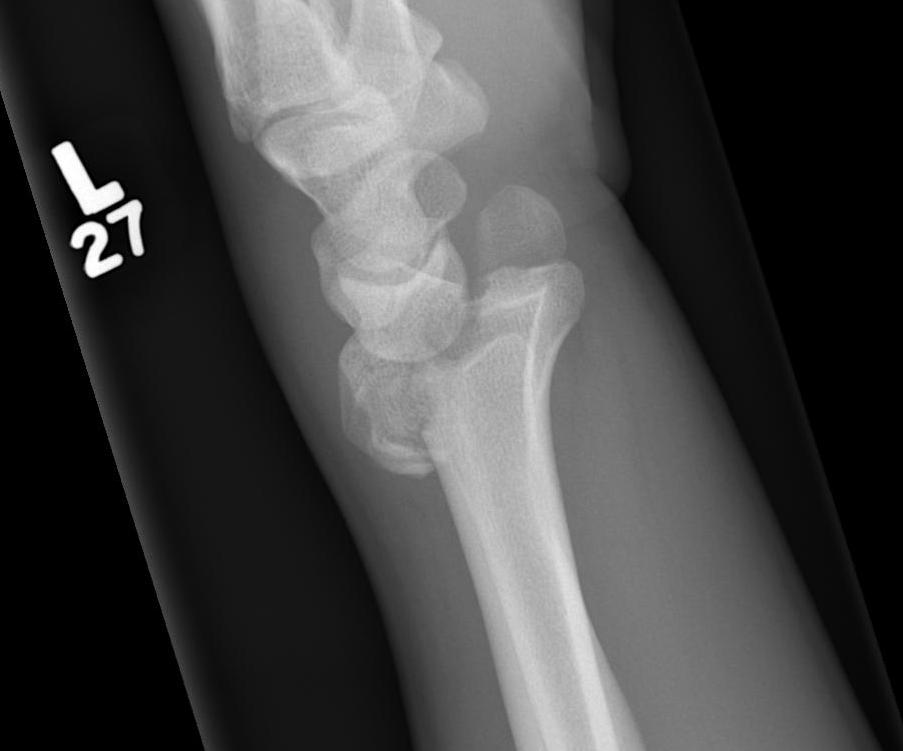

DRDR

Dr shortDR short

Distal radius fracture with shortening and dorsal tilt